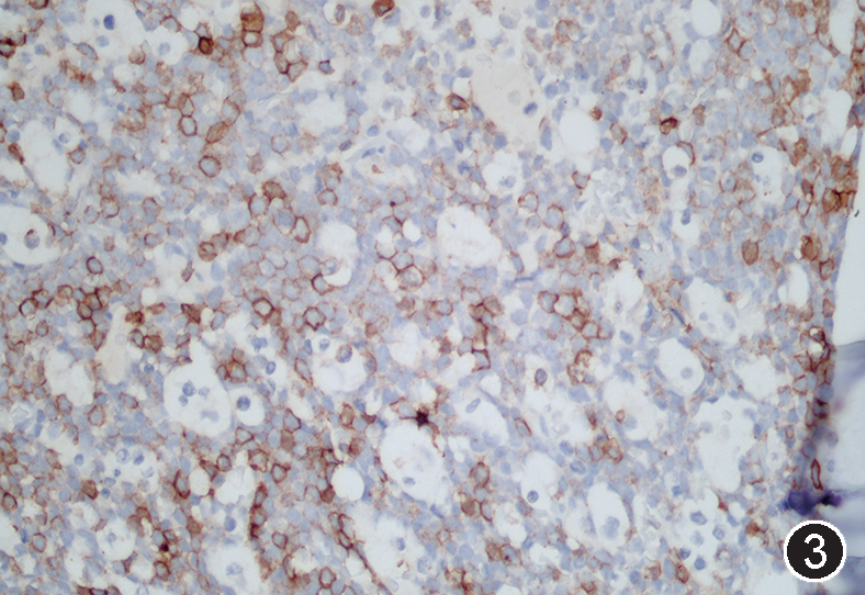

图注:图1 骨髓涂片中的肿瘤细胞(瑞氏染色,×1 000);图2 骨髓活检中的肿瘤细胞(HE, 高倍放大);图3 免疫组织化学染色,CD20部分阳性(EnVision法,中倍放大);图4 免疫组织化学染色,CD19阳性;图5 免疫组织化学染色,CD10阳性;图 6 免疫组织化学染色,MYC阳性,图 7 免疫组织化学染色,bcl-2阴性;图 8 免疫组织化学染色,Ki-67阳性指数约 80%。

根据以上检查结果,需要考虑的淋巴瘤类型包括BL、HGBL、原始细胞标记阴性B-ALL(占B-ALL<5%)以及罕见CD5-CD10+MCL的母细胞变型,须进一步进行免疫组化(包括CyclinD1、CD10、BCL6、MUM1、MYC、BCL2、Ki67)、染色体核型、FISH检测(MYC、BCL2、BCL6、IgH-CCND1)以及白血病融合基因检测加以区分。最终流式细胞学示肿瘤细胞CD38强表达、表达sIgM、sIgD和胞膜Kappa,免疫组化CyclinD1-,细胞遗传学示复杂核型,FISH检测MYC和bcl-6基因重排阳性,白血病52种融合基因阴性,二代测序提示存在TP53、CCND3、MYC、TCF3、FOXO1等HGBL、DLBCL中而非B-ALL/LBL中的常见基因突变类型,因此综合诊断为HGBL伴MYC和bcl-6基因重排。